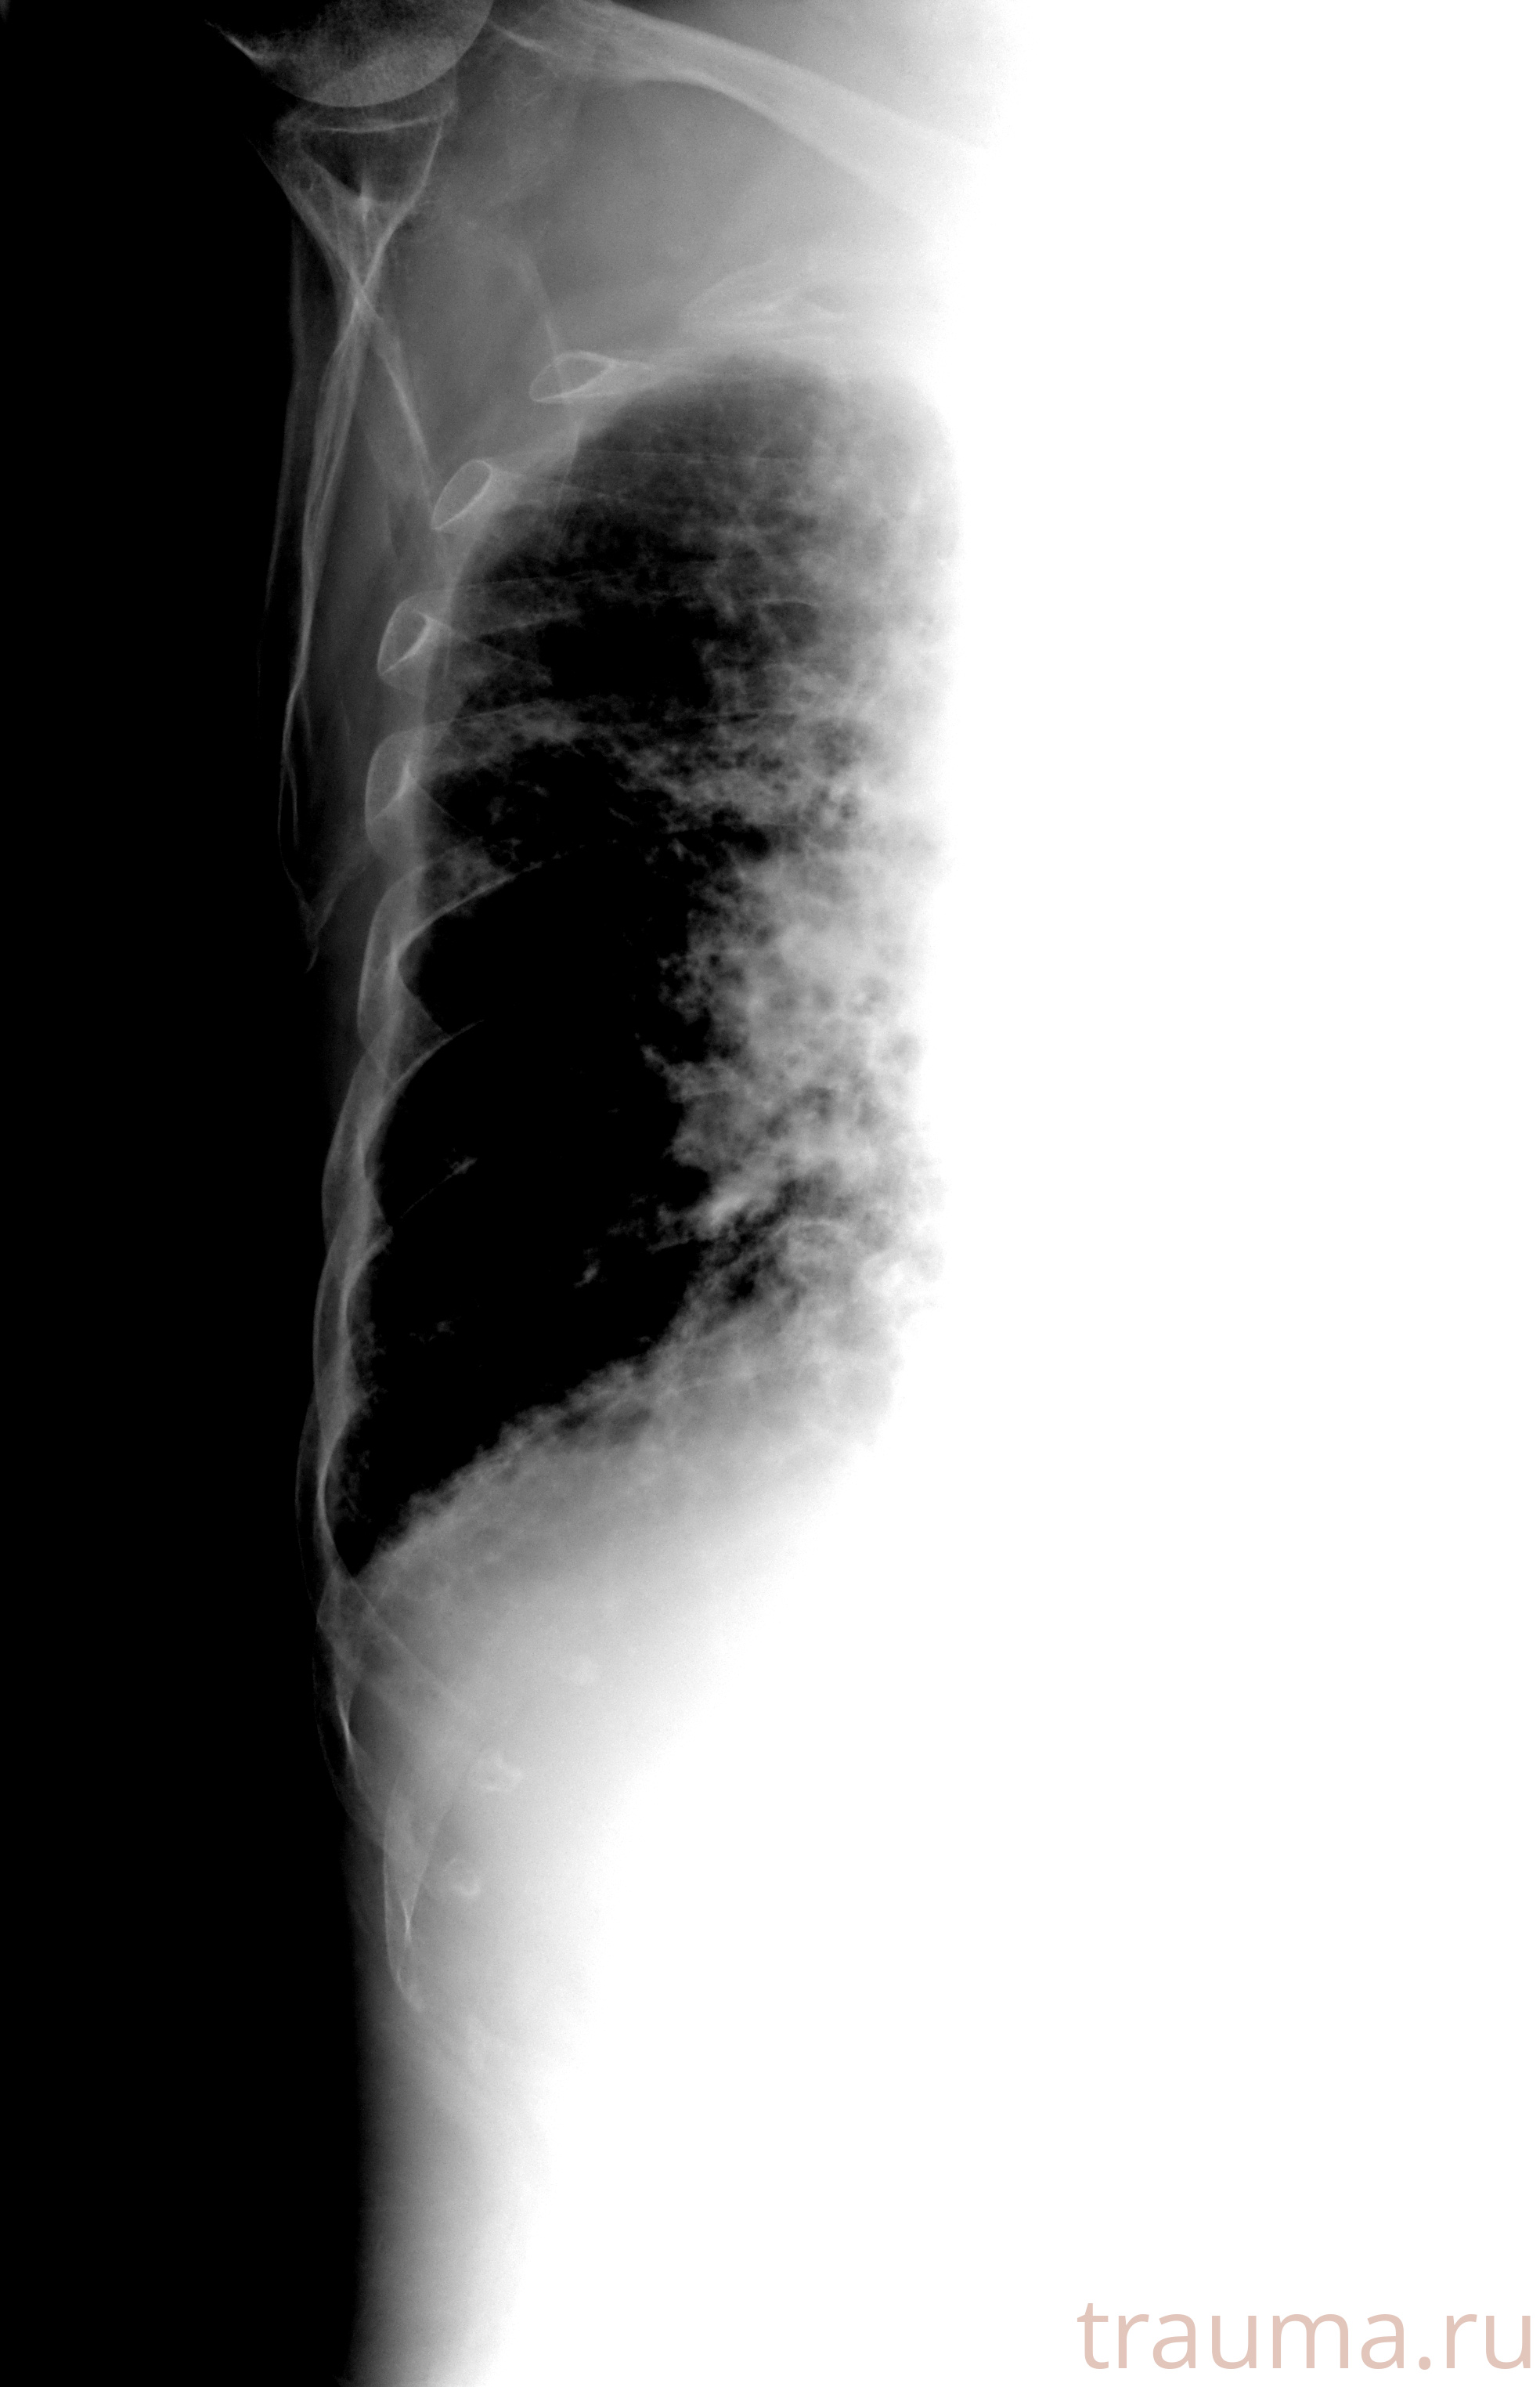

Рентген на дому: по вашему адресу приезжает врач-рентгенолог, травматолог-ортопед с мобильным рентгеновским аппаратом, проводит диагностику травмы или заболевания, делает необходимые рентгенограммы, дает рекомендации по дальнейшему лечению. Получить качественные снимки в домашних условиях возможно благодаря уникальной методике, разработанной МосРентген Центром для института  Склифосовского

при переломе шейки бедра и пневмонии от компании МосРентген Центр - партнера Института имени Склифосовского